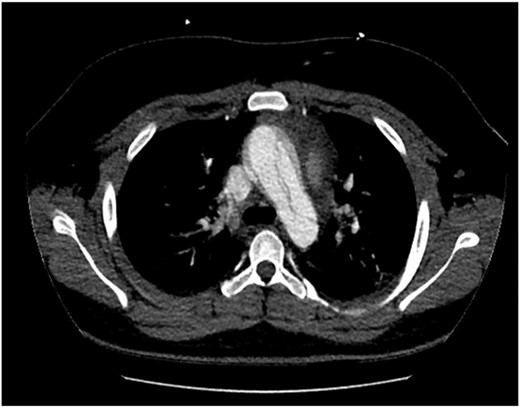

The patient was hemodynamically stable during his admission; however, worsening pain profile led to a serial electrocardiogram showing sinus rhythm with ST segment changes consistent with ischemia. There was an initial troponin rise of 245 ng/L progressing to a peak of 922 ng/L. The remaining blood panel was unremarkable. Chest X-ray showed no widened mediastinum and clear lung fields. A bedside transthoracic echocardiogram demonstrated a dissection flap with severe aortic regurgitation in the ascending aorta. Computed tomography aortogram was consistent with a Stanford Type A aortic dissection extending from the aortic root to the bifurcation of the common iliac arteries (Figs 1 and 2). There was involvement of the right brachiocephalic artery and right common iliac.

Computed tomography aortogram Axial Image of Stanford Type-A Aortic Dissection.